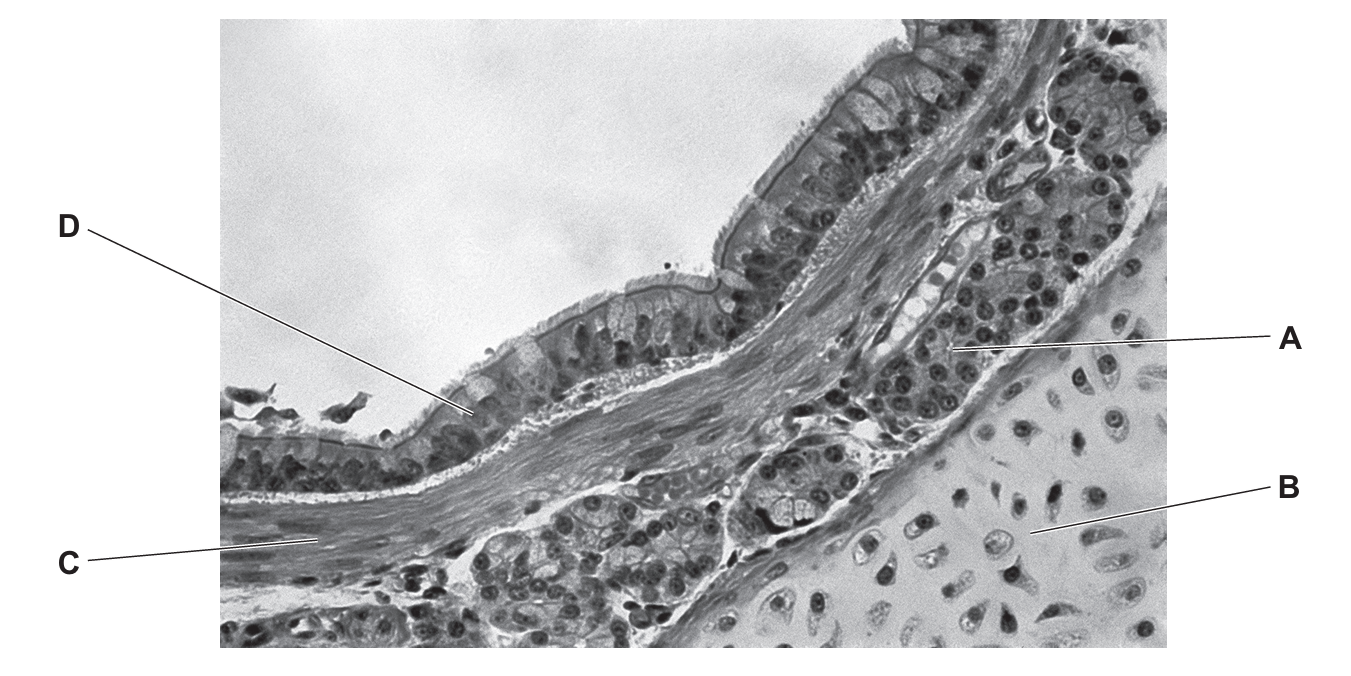

The photomicrograph shows part of a bronchus.

Which label identifies cartilage?

▶️ Answer/Explanation

Ans: B

In the bronchus, cartilage appears as C-shaped rings that provide structural support. The label B correctly identifies this characteristic cartilage structure, while label A likely points to other tissues like smooth muscle or epithelium.